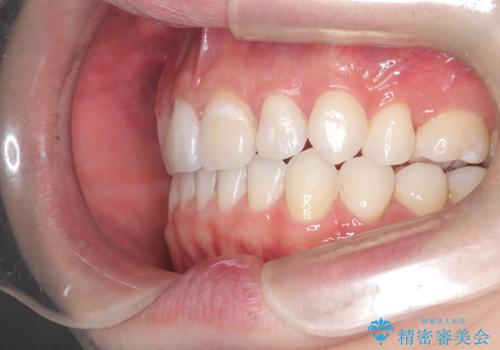

- 前歯が出ていることを主訴に来院されました。

臼歯関係が上顎前突傾向のため、上顎小臼歯を抜歯してインビザラインにて治療を行いました。

臼歯の咬合を作るために治療終盤ではゴムかけを行なっています。